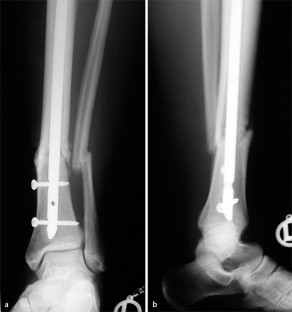

Abb. 2